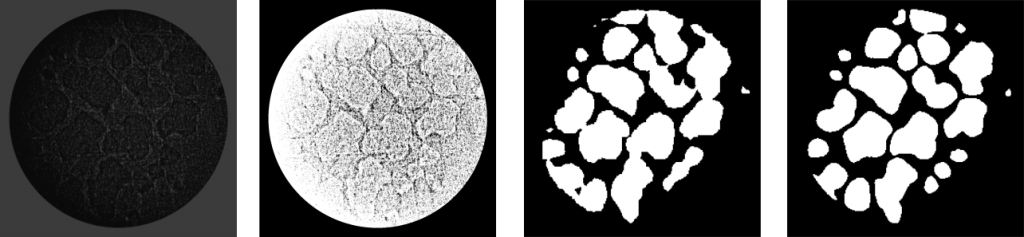

In the past, the biggest efforts were devoted to the reconstruction of the conducting airways network in three dimensions (3D) from three-dimensional X-ray or CT images. Important role of 3D reconstruction of parenchyma is the study of micromechanics in 3D acinar microarchitecture and airflow through it with the help of computational fluid dynamics. In general, 3D reconstruction of a human pulmonary acinus enables simulating and quantifying regional deposition effects. This task is important in the pulmonary delivery of drugs intended for the topical treatment of respiratory ailments and in situation when lung bioavailability is limited. This task is also important from the perspective of modeling acinar convective airflows and testing their role in determining the fate of inhaled aerosols in the distal regions of the lungs. This way, a patient specific diagnosis and therapy can be conducted. Here we present our new efforts on automatic recognition of alveoli in parenchyma on extracted images as a precondition for 3D reconstruction of acinar air space. The automatic pulmonary acinus (ducts and sacs) segmentation of rat lungs has been done using U-Net based deep convolutional network.

Stereologically well characterized rat lung samples were imaged using high-resolution synchrotron radiation-based X-ray tomographic microscopy cite{tsuda2008}. As a result, a stack of lung images was generated. Each slice has a size of 1350 x 1350 pixels. These slices had been downsampled to 256 x 256 before they were fed to U-Net. In total, in our dataset we have only 101 labeled (with mask) images, and they belong to different positions in the stack. </p><p>Data augmentation is essential to teach the network the desired invariance and robustness properties, when only a few training samples are available. Because there are not enough images in the training set (only 101 are available), image data augmentation technique is used to artificially expand the size of a training dataset by creating modified versions of images in the dataset. These techniques can create variations of the images that can improve the ability of the fit models to generalize what they have learned to new images. In this way, we can obtain more skillful model.